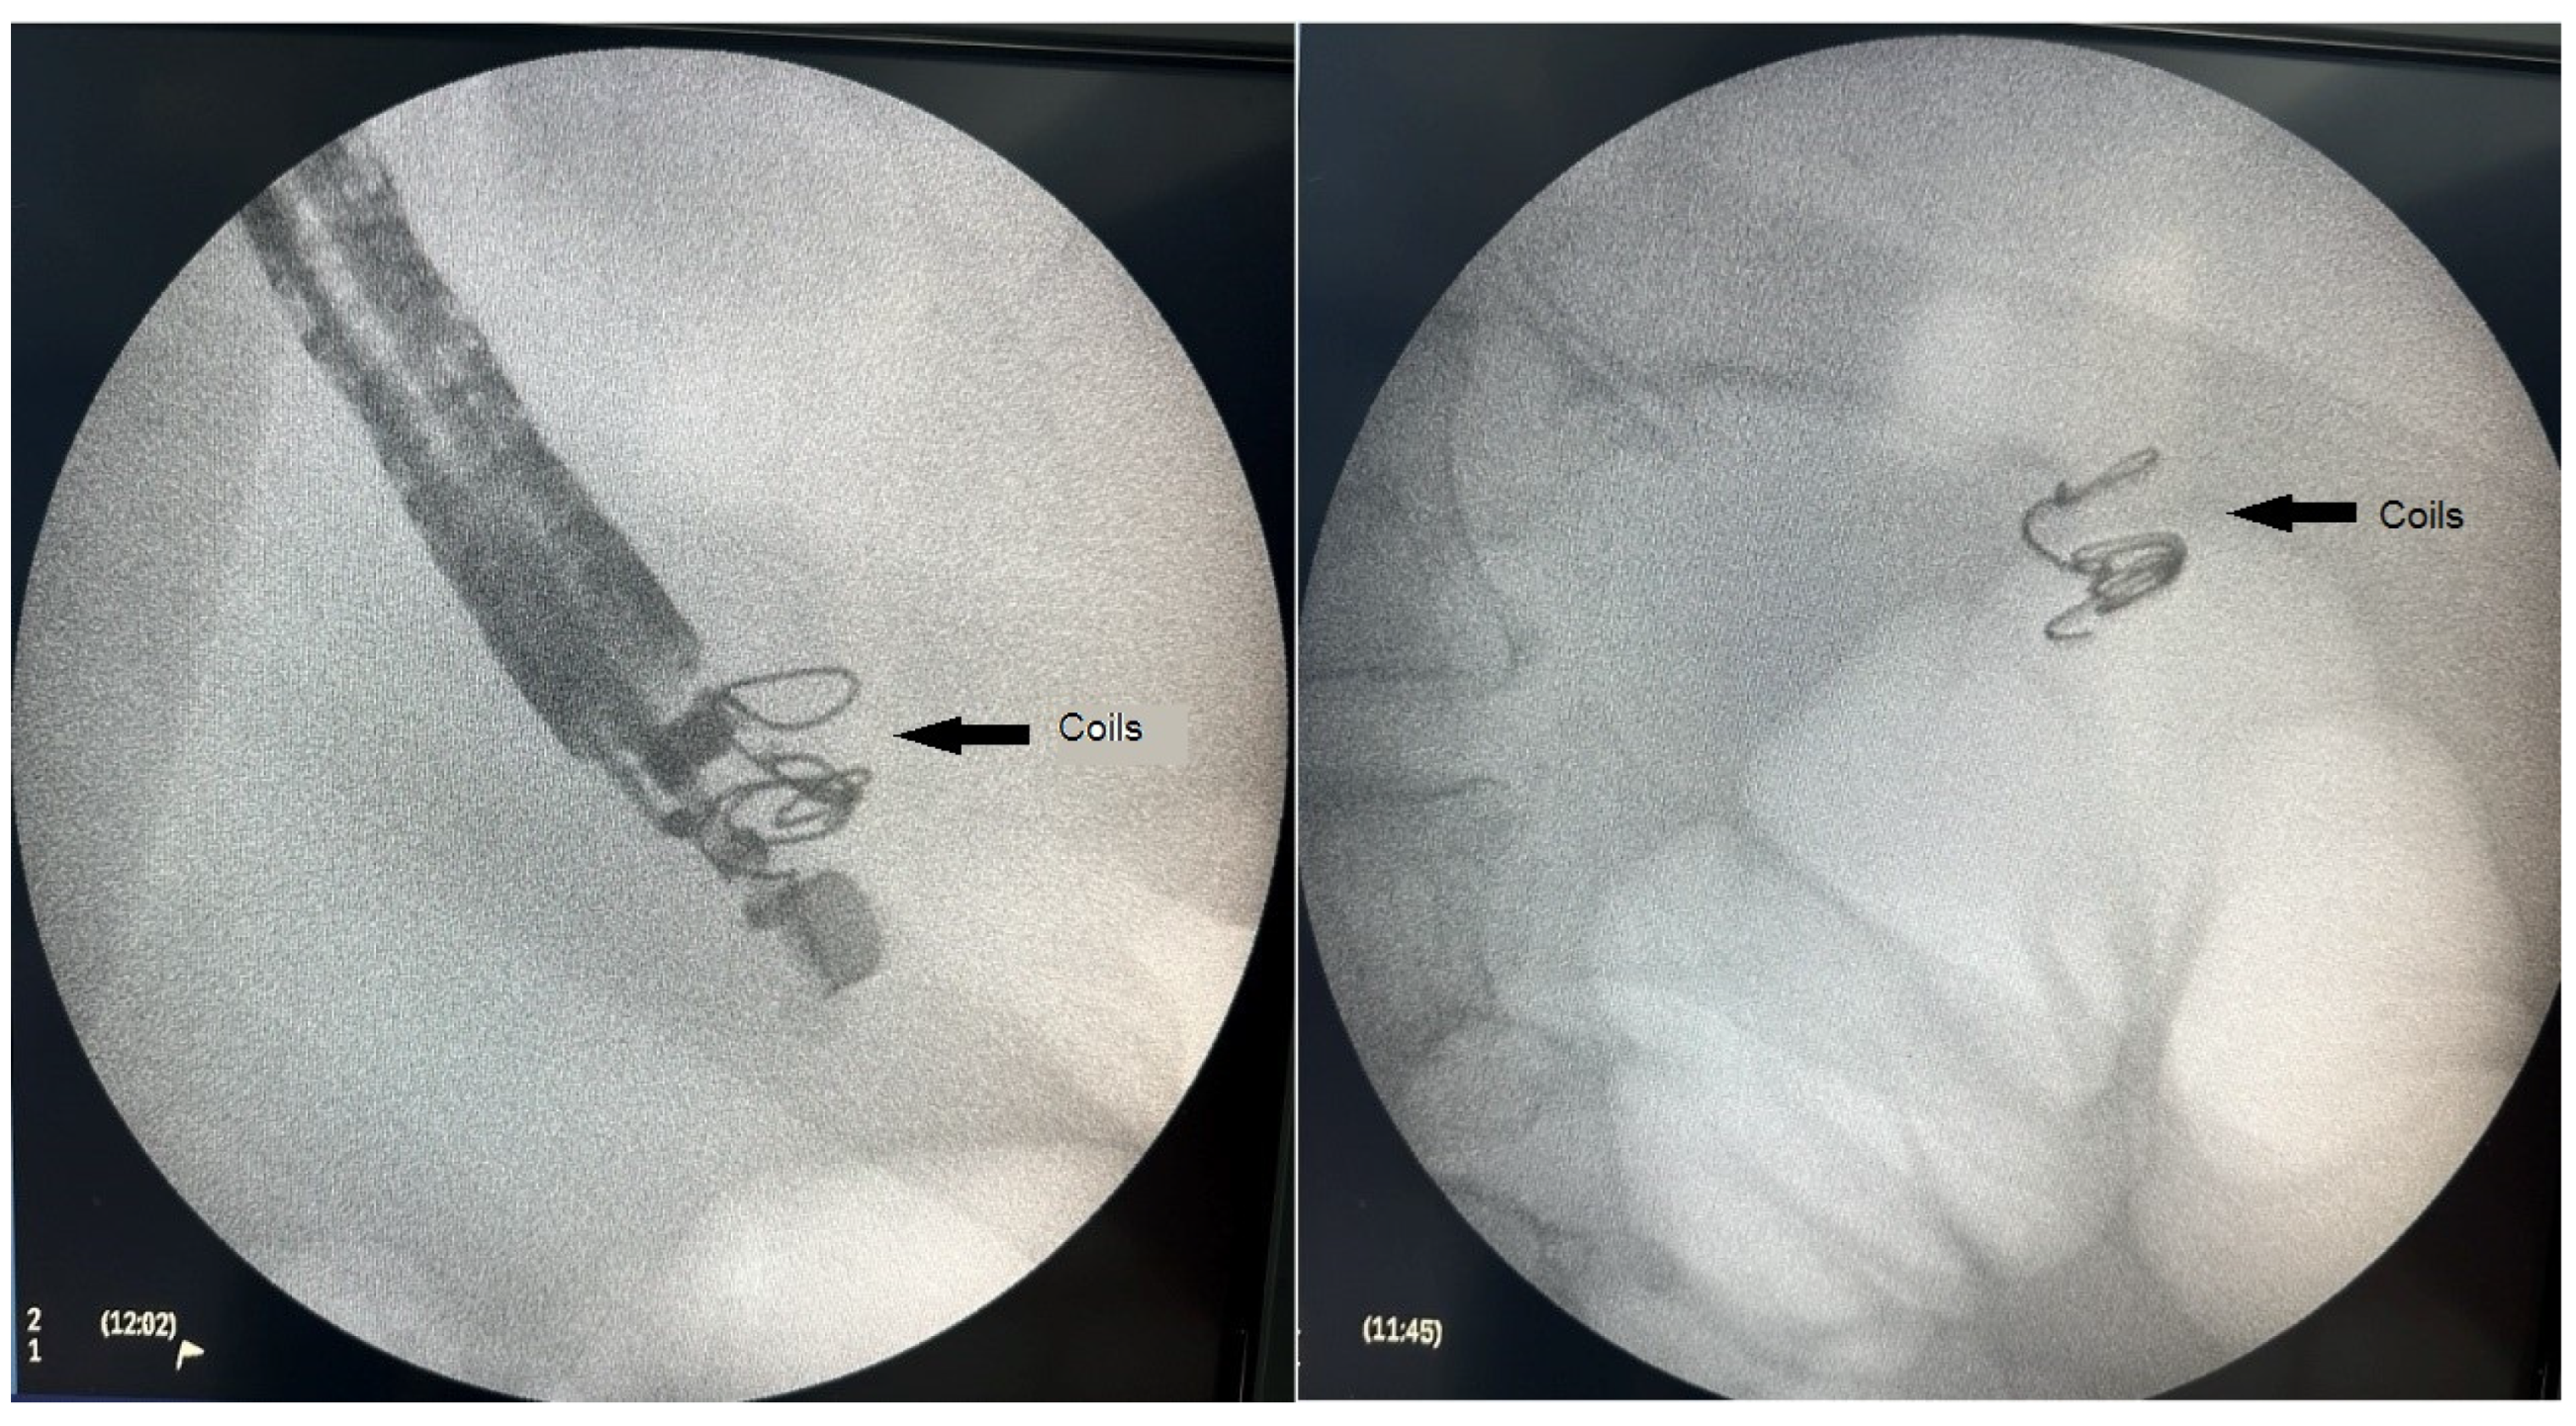

Figure 1, Figure 2 and Figure 3 present post-procedural endoscopic, endosonographic, and fluoroscopic findings.

Figure 3.

Fluoroscopic image of the introduced embolization coils.

Once an adequate position was achieved sonographically, the varix was punctured with a 19 Ga fine needle aspiration (FNA) needle (ExpectTM needle; Boston Scientific, Marlborough, MA, USA). As anticipated, a transgastric approach was associated with a more angulated position of the tip of the endoscope, leading to a more difficult puncture of the target vessel and insertion of the coils. Blood was aspirated to verify an adequate position, followed by rinsing the needle with 4 mL of 5% glucose solution. Next, two 0.035 inch 14 mm/7 cm embolization coils (Nester Embolization coil; Cook Medical, Bloomington, IN, USA) were introduced into the varix. The technique consisted of inserting the coils into the FNA needle, and then pushing them out into the varix using a needle stylet. The procedure was executed under combined ultrasound and fluoroscopic guidance using Philips BV Pulsera C-arm (Philips, Best, The Netherlands). Although primarily used as a scaffold for subsequent glue injection, an immediate reduction of blood flow in the varix was observed upon coil deployment.

The standard approach to coil introduction involves positioning the puncture needle at a distance from the opposite wall of the vessel to reduce perforation risk [26]. The diameter of the coils should be 20–30% larger than the diameter of the vessel to preclude migration [26]. We followed those recommendations with the largest diameter of the varix being 10 mm. We also used two 14 mm/7 cm 0.035″ embolization coils.